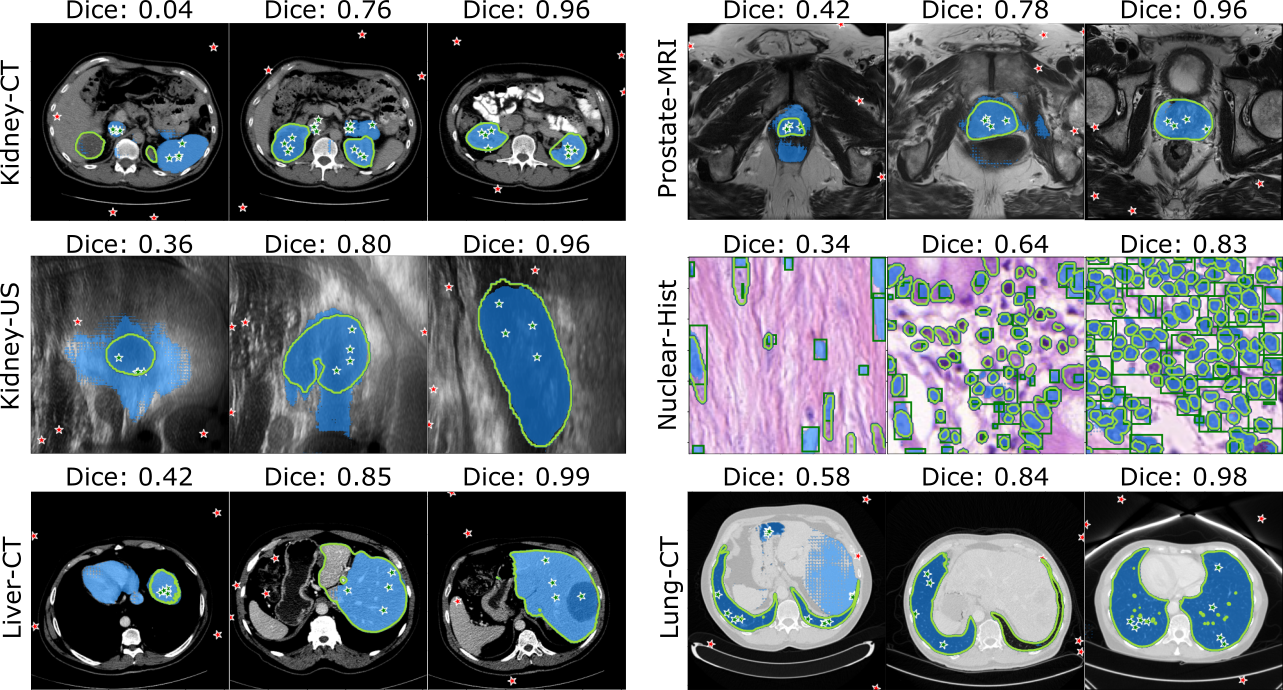

As for the ‘coarse segmentation’ strategy, annotated slices will be divided into support and query sets in the training stage. In the inference stage, all annotated slices will be used as support set. Additionally, during the inference phase, we employ a post-processing step by extracting the top-K components from the coarse segmentation results to further mitigate FPs. The segmentation results of the SAM are depicted in Figure 12, while the visualization of these segmentation results can be observed in Figure 13. For each dataset, it presents three examples from left to right, progressing from left to right, illustrating segmentation performances ranging from poor to excellent. Noticed that all dataset used points as input prompts except for the Nuclear-Hist dataset, which used boxes as prompts.

In comparison, our proposed SAM with SAP-Net backbone demonstrated superior performance. Trained with only five annotated slices, SAM achieved compatible performance with SAM , which is semi-automatic approach. For instance, average Dice coefficients of 0.84, 0.92 and 0.91 were achieved on Kidney-CT and Liver-CT and Lung-CT datasets, respectively. However, there remains space for improvement on challenging Nuclear-Hist dataset.

Although we introduced biased Dice loss to suppress the FPs, the FPs still remain as the biggest issue of the few-shot based approach. Consequently, by implementing a simple post-processing, the final segmentation performance of large solid organs exhibits a remarkable improvement, as shown in Figure 12. However, this simple post-processing can be only applied to the targets with a fixed number. Table 5 demonstrated the effectiveness of our introduced features, successfully improve the baseline (vanilla PANet) from 73.2% to 84.0%. Several segmentation results of Kidney-CT are visualized in Figure 15.